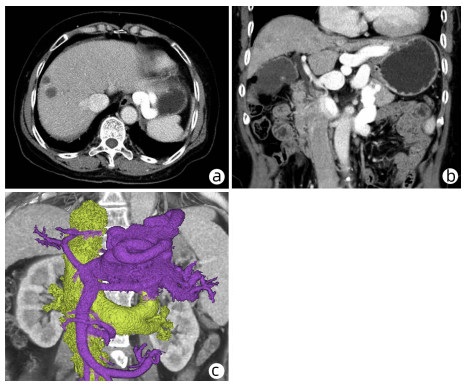

Clinical features of patients with portal hypertension due to Abernethy malformation: An analysis of 5 cases

Tingting BAI, Qin LI, Liangzhi WEN, Yanmei ZHANG, Yanling WEI, Bin WANG, Dongfeng CHEN, Hanyang XING

2023, 39(3): 620-625. DOI: 10.3969/j.issn.1001-5256.2023.03.020

Abstract(654) HTML (347) PDF (3579KB)(108)

Abstract: